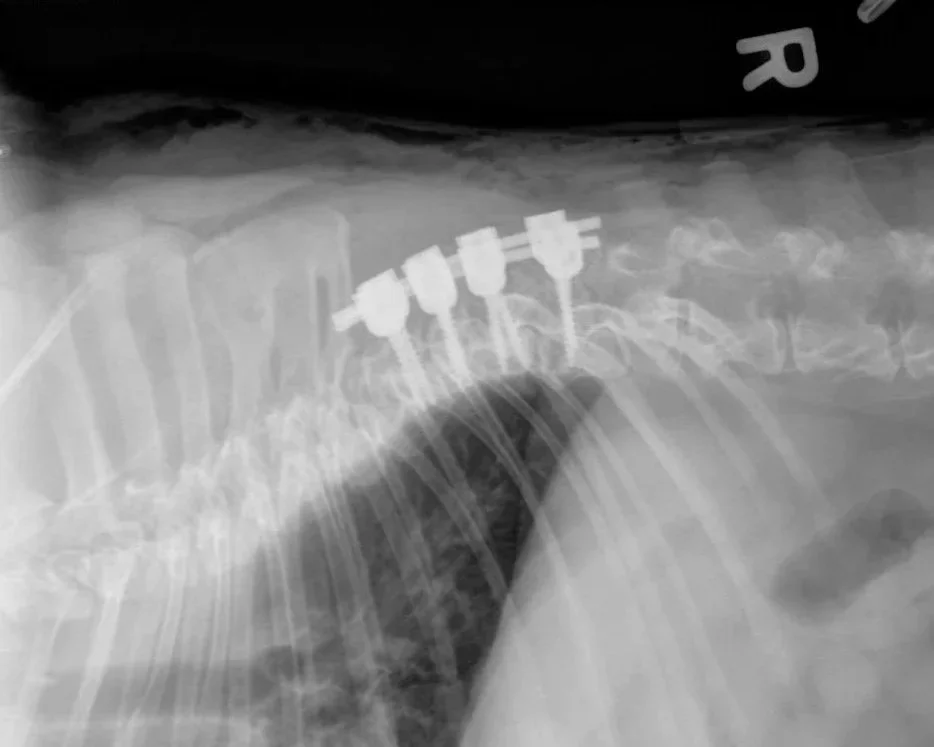

5 kg Pug subtotal corpectomy with stabilization

7 kg French Bulldog dorsal laminectomy with stabilization

8 kg Shih Tzu, C5 - C7 stabilization

8 kg French Bulldog, dorsal laminectomy and stabilization